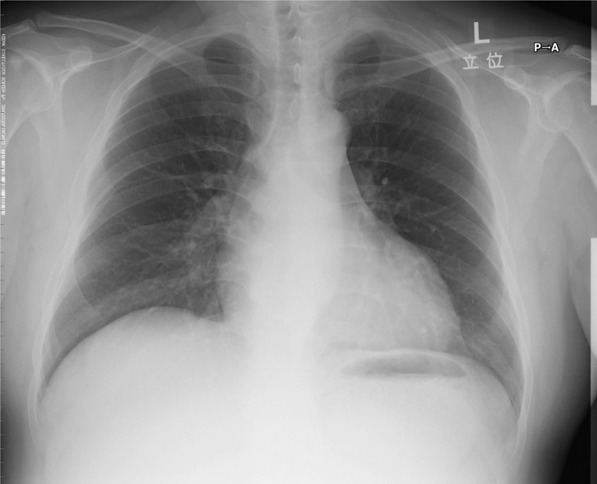

問題の心電図は洞頻脈、V1で典型的な左房負荷の所見を認め、左室の電位は高く、左室誘導(I、aVL、V5−6)でsagging型のST低下とT波の逆転を認める。典型的な圧負荷に対する左室肥大の所見である。左房負荷の存在から長期間の圧負荷と左心不全の存在が示唆される。来院時の身体所見は、血圧が高く頻脈。心臓では3音、4音がsummation gallopとして聴取されている。急性左心不全による肺水腫の状態である。胸部X線では、心陰影は拡大、左室の拡大と肺血管の再分布を認める。

胸部X線画像